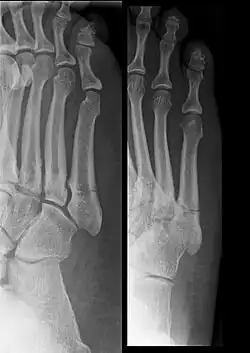

![]() Złamanie nasady V kości śródstopia |

Zdjęcie rentgenowskie rzadko pozwala uwidocznić mikrozłamania, co daje 70% wyników fałszywie ujemnych. Badania radiologiczne złamania przewlekłego może (ale nie musi) ujawnić dyskretną szczelinę złamania z dominującym obrazem obfitej kostniny o wrzecionowatym kształcie. Rzadziej, gdy przeciążenia lub mikrourazy były silniejsze, a do złamania doszło w krótszym czasie, szczelina bywa wyraźnie widoczna. Wczesną fazę złamania zmęczeniowego może ujawnić scyntygrafia kośćca.